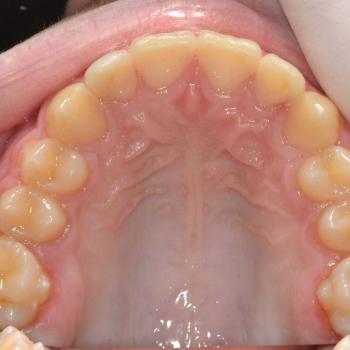

Balázs és édesanyja konzultáció céljából keresett fel, hogy egyértelműen kiderüljön számukra szükséges-e a fogszabályozó kezelés vagy sem. Már rögtön az első vizsgálat alkalmával fény derült több olyan problémára is, melyek fogszabályozást igényelnek. Ilyen volt például a súlyos mélyharapás, a hátrafelé dőlő felső metszők, illetve az Angle II. osztályú harapási eltérés is. A mintavétel, a röntgenek és a fotók kiértékelése után további problémaként merült fel a felső fogív szűkülete és a kismetszők méretaránytalansága, azaz a túlzott keskenységük.

A kezelést Quadhelix fogszabályozóval kezdtük el a felső fogív tágítása érdekében. Ezután került felragasztásra az alsó és felső fogívre a Balázs és szülei által kiválasztott fém önligírozó fogszabályozó. Ezen túlmenően Bite turbo harapásemelő segített a mélyharapás, intermaxillaris gumihúzás pedig az Angle II. osztályú harapási eltérés korrigálásában. A fogak méretaránytalansága miatt a kezelés végén a kismetszőket tömőanyaggal építettük fel, hogy a tökéletes harapáshoz résmentes fogazat társuljon. A fogak felépítéséhez az adott fogakat nem kell megfúrni, a tömőanyag kizárólag ragasztásos módszerrel rögzül, így nem károsodik a fogzománc.